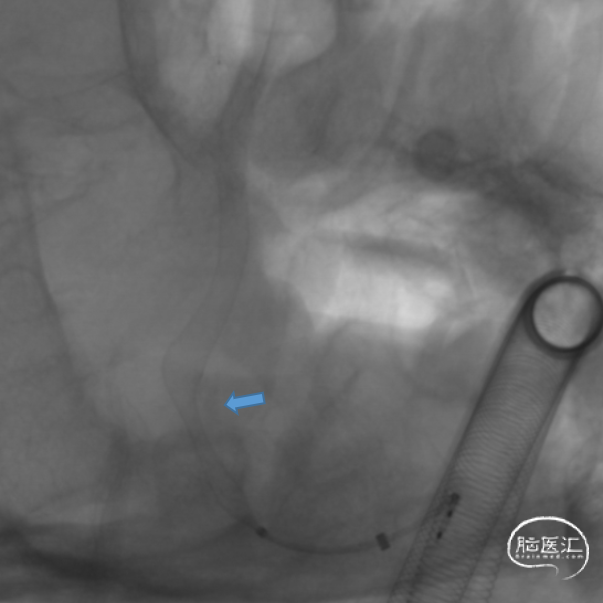

J-Tube™血流导向密网支架释放后处理狭窄。

Gateway 3.5*15 球囊到位

充盈球囊

球囊后处理效果。

处理前

处理后